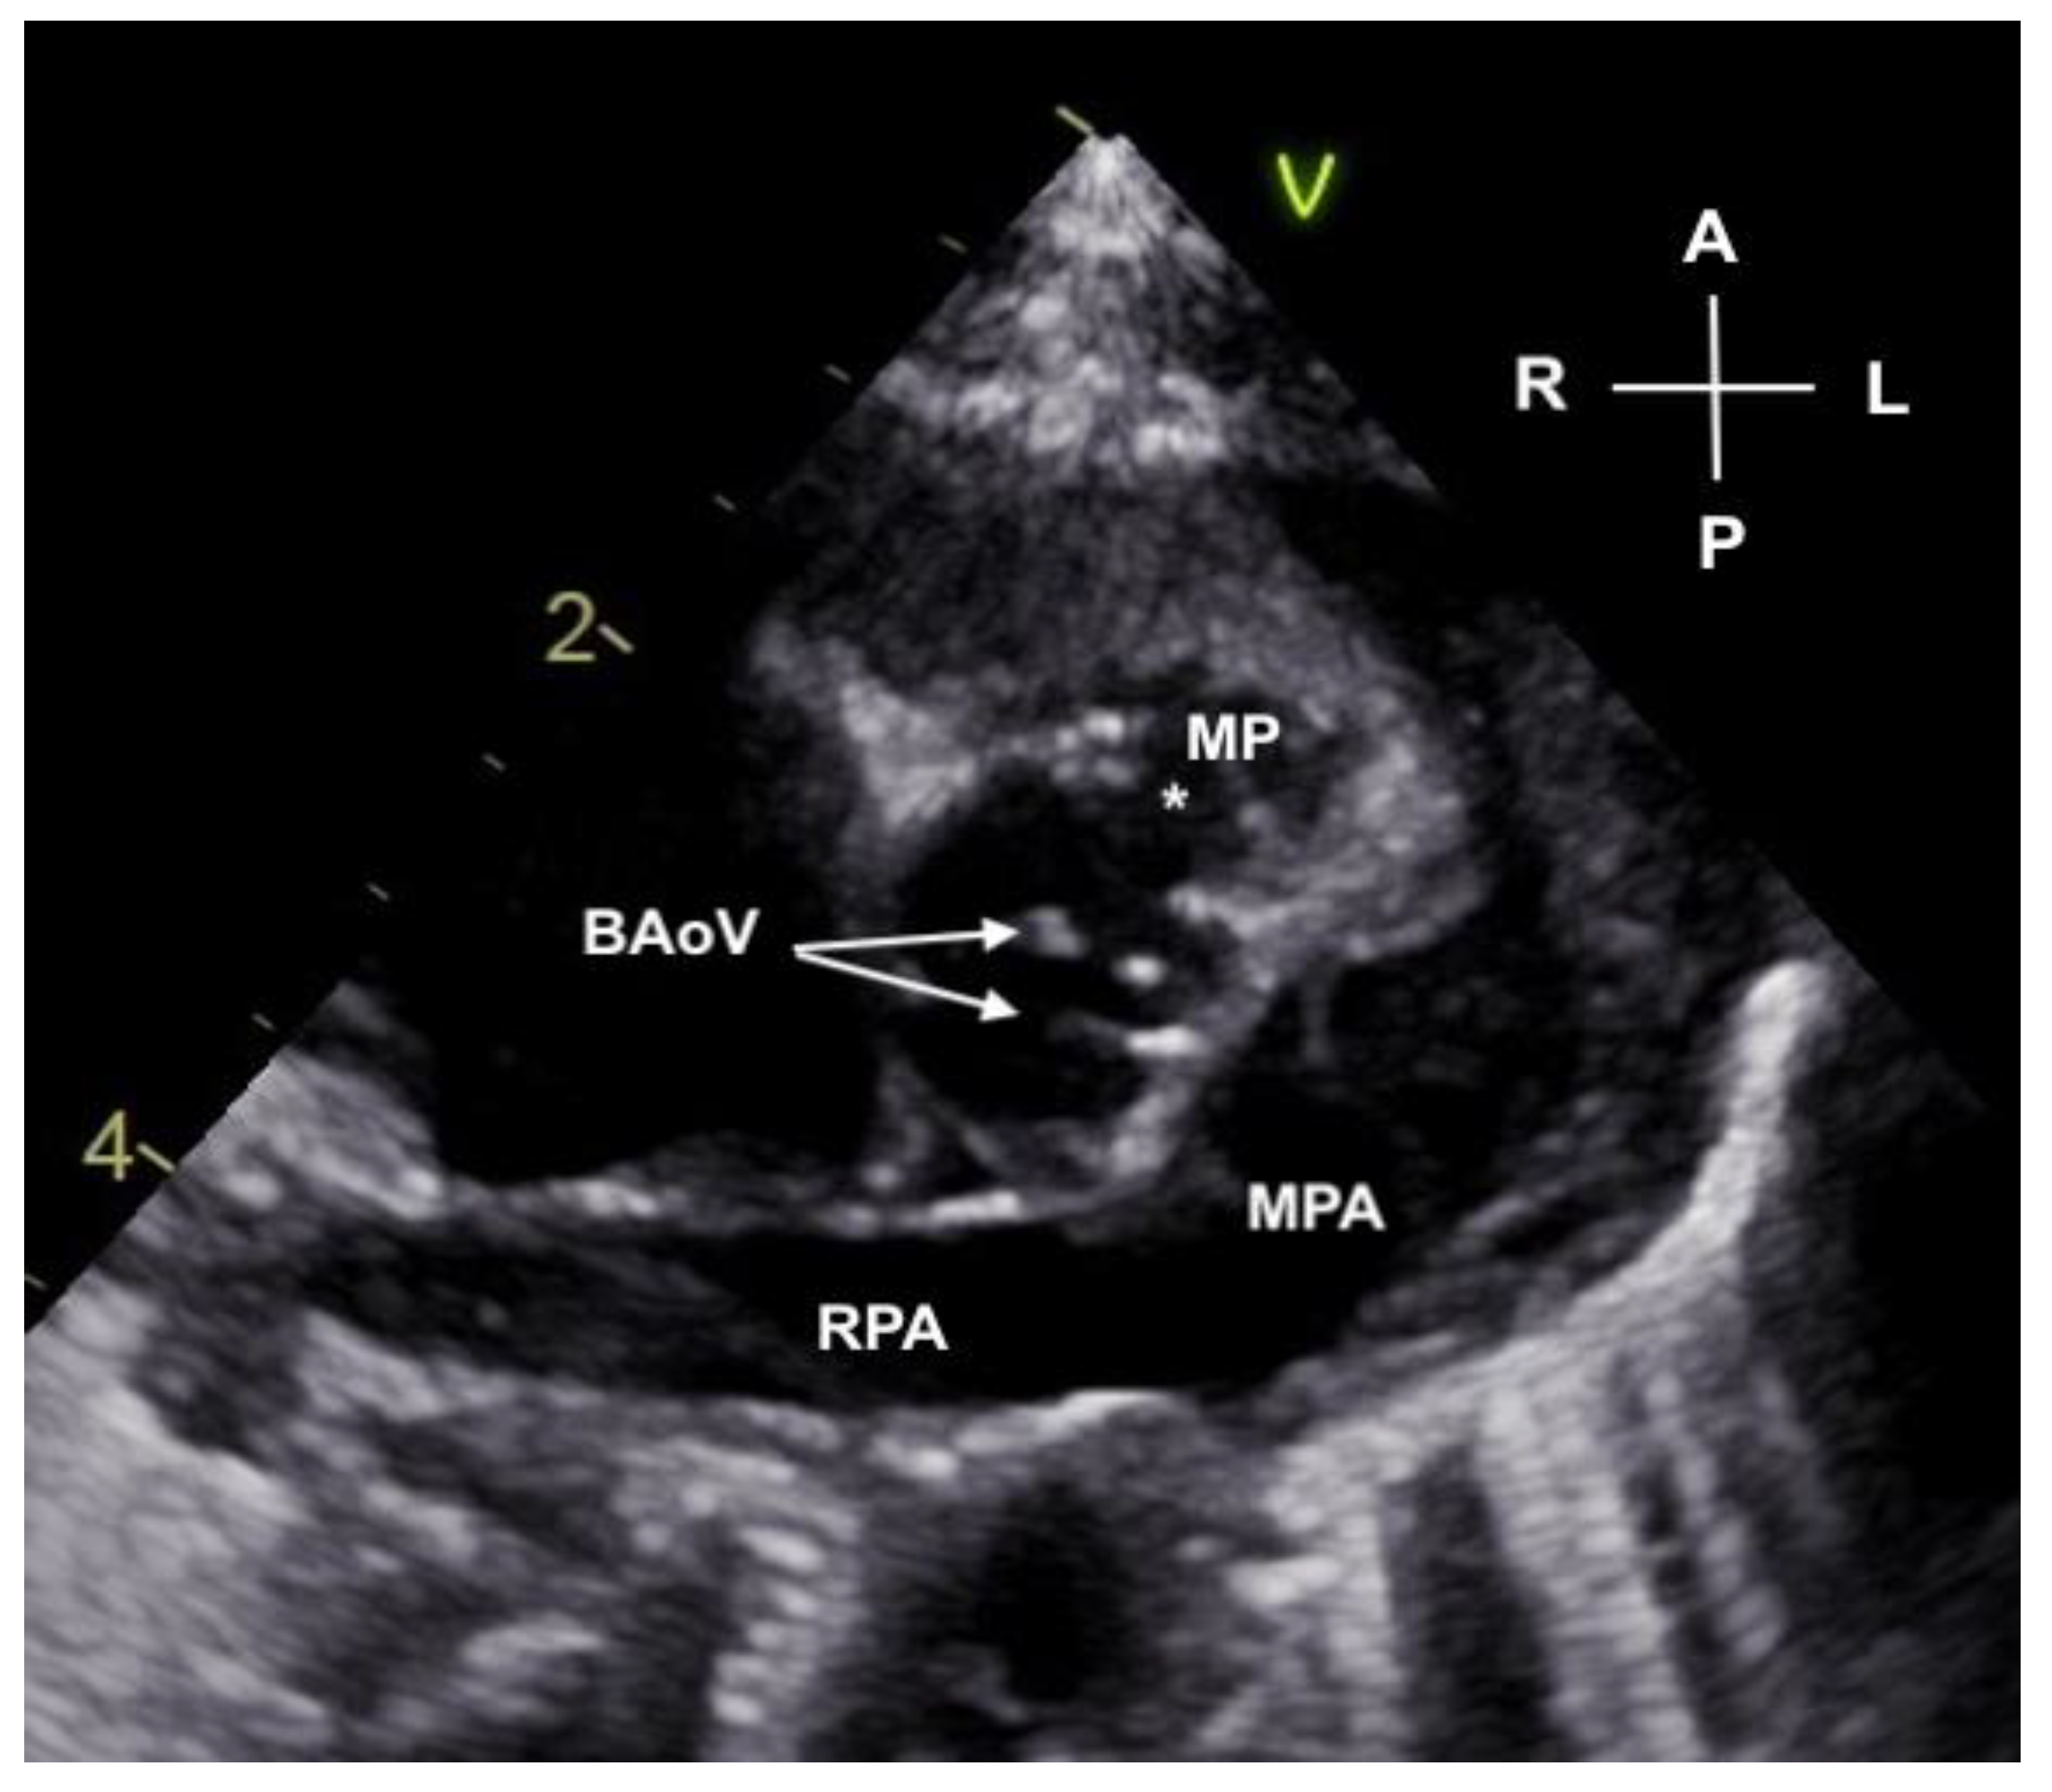

2. Case Description